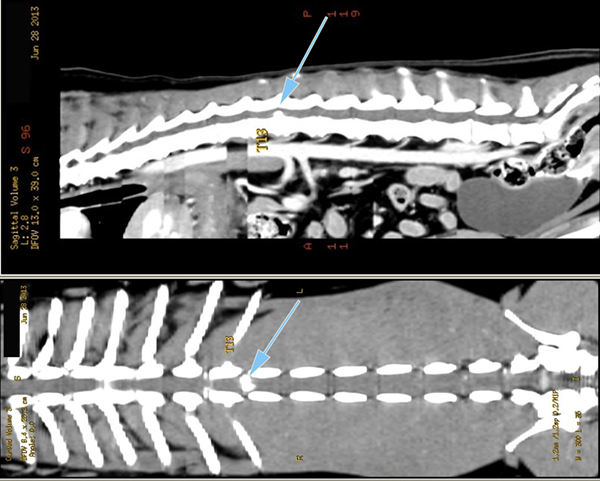

Myélographie Hernie Discale T12-T13

La myélographie est souvent suffisante pour établir un diagnostic et poser l'indication chirurgicale, cependant dans certains cas, en présence d'un gros oedème médullaire ou de difficultés de latéralisation, il peut être nécessaire d'avoir recours à des moyens d'imagerie tridimensionnels comme le scanner ou l'IRM.

Les imprécisions liées au caractère bidimensionnel de l'examen le rend actuellement obsolète face à la tomodensitométrie numérisée. Son usage peut encore se justifier en situation d'urgence neurologique chirurgicale et en l'absence de disponibilité d'un scanner. La myélographie, avec ses carences, demeure un examen utile, tant par sa simplicité de réalisation que par sa grande accessibilité matérielle (un simple appareil de radiologie permet d'y avoir recours).

Le Scanner ou Tomodensitométrie Numérisée.

Le scanner est actuellement l'examen de choix pour le diagnostic des hernies discales chez les carnivores domestiques et d'une façon générale pour l'exploration des pathologies du rachis. Ses capacités de dessuperposition des structures anatomiques et sa meilleure résolution spatiale lui permettent, avec les machines de dernière génération, de supplanter définitivement les examens radiologiques sous contraste.

Le scanner permet à la fois une meilleure approche de l'étage de la lésion, mais aussi une meilleure latéralisation de celle-ci, ce qui est capital en cas de geste chirurgical. Il permet aussi, en cas de hernies multiples (ce qui est fréquent dans certaines races comme le Bouledogue français) d'avoir une approche lésionnelle permettant, au travers de critères objectifs, de faire un tri entre les hernies pour isoler celle responsable des symptômes nerveux.

L'examen tomodensitométrie du rachis se fait avant et après injection de produit de contraste iodé pour rehausser les lésions. Dans certains cas extrêmes, et au demeurant rarissimes, une injection complémentaire de produit de contraste dans l'espace sous arachnoïdien peut être nécessaire, l'examen réalisé alors se nomme un myéloscanner. Cet examen peut s'avérer très utile, notamment pour le diagnostic de certaines affections rares des méninges nommées kystes arachnoïdiens, présentes en particulier chez le Rottweiler, et dont le diagnostic constitue une des limites du scanner avec le syndrome de Chiari.

Coupes axiales

Scanner d'une Hernie discale T13L1 extrusive chez un chien reformatages sagittal et coronale